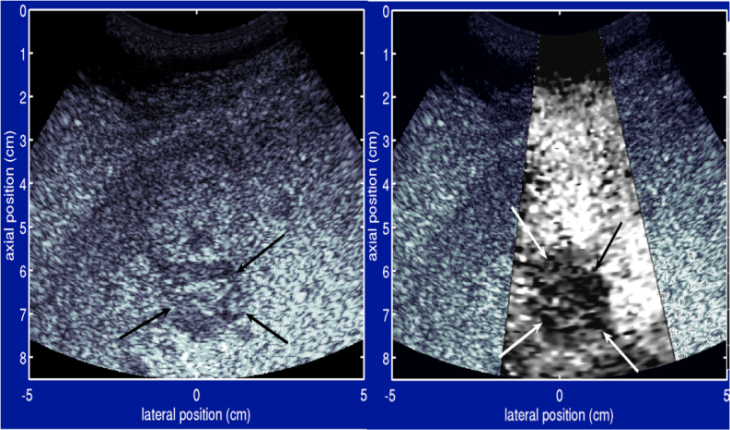

Otra forma funcional del ultrasonido es la elastografía, un método para medir y desplegar la rigidez relativa de los tejidos, la cual se puede utilizar para diferenciar los tumores de tejido sano. Esta información se puede desplegar como mapas codificados por color de la rigidez relativa; mapas en blanco y negro que despliegan imágenes de alto contraste de los tumores, comparadas con las imágenes anatómicas; o mapas codificados por color superpuestos en la imagen anatómica.

Imágenes de Radiación Acústica por Impulso de Fuerza (ARFI por sus siglas en inglés). ARFI es una técnica nueva desarrollada con apoyo del NIBIB que utiliza elastografía de ultrasonido para diferenciar los tumores hepáticos del tejido sano, así como para identificar la presencia de fibrosis. Este método no invasivo podría reducir las biopsias de hígado innecesarias, las cuales pueden ser dolorosas y a veces peligrosas. Actualmente, la técnica ARFI está siendo sometida a revisión por la FDA para su uso eventual en hospitales y clínicas.De clic aquí para leer más acerca de la técnica ARFI.

- Fahey y otros. “Visualización in vivo de malignidades abdominales con elastografía por fuerza de radiación acústica”, Fís. Med. Bio. 53 (2008) 279-293.